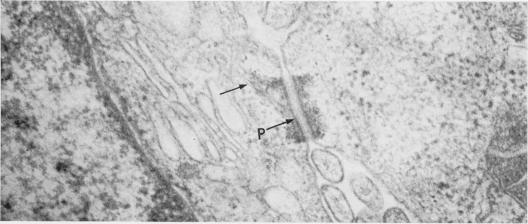

Rat ascites hepatoma AH109A cells (present as a free form in vivo) can aggregate and then develop well-defined tripartite junctional complexes, including intermediate junctions, desmosomes and focal tight junctions, on incubation with a glycoprotein separated from rat ascites hepatoma AH136B cells (forming cell islnds in vivo). The development of binding structures was strongly inhibited by actinomycin D. AH109A cells or rat ascites hepatoma YS cells (present as a free form in vivo) previously treated with the glycoprotein for 24 h, when inoculated i.p., proliferated as free cells in the ascitic fluid, like the untreated cells. AH109A cells actively proliferating in the skin do not form any junctional complexes. The reason for the failure of island formation by AH109A cells or YS cells in vivo is discussed.

大鼠腹水肝癌AH109A细胞(在体内以游离形式存在)在与从大鼠腹水肝癌AH136B细胞(在体内形成细胞岛)分离的一种糖蛋白一起孵育时,能够聚集,然后形成明确的三联连接复合体,包括中间连接、桥粒和紧密连接。结合结构的形成受到放线菌素D的强烈抑制。预先用该糖蛋白处理24小时的AH109A细胞或大鼠腹水肝癌YS细胞(在体内以游离形式存在),腹腔注射接种后,会像未处理的细胞一样在腹水中以游离细胞的形式增殖。在皮肤中活跃增殖的AH109A细胞不形成任何连接复合体。文中讨论了AH109A细胞或YS细胞在体内未能形成细胞岛的原因。